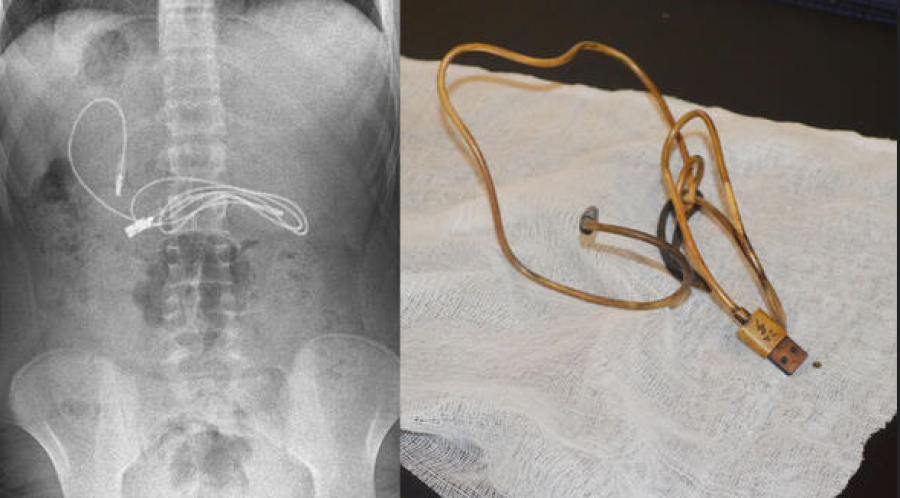

Diyarbakır'da kusma ve bulantı şikayetiyle hastaneye götürülen, çekilen röntgeninde 1 metrelik şarj kablosu ve toka yuttuğu tespit edilen 15 yaşındaki erkek çocuğu, Elazığ'da gerçekleştirilen operasyonla yuttuğu cisimlerden kurtuldu.

Diyarbakır'da kusma ve bulantı şikayetiyle ailesi tarafından hastaneye götürülen erkek çocuğunun çekilen röntgeninde, midesinde şarj kablosu ve toka olduğu tespit edildi. Bunun üzerine çocuk, ambulans ile Fırat Üniversitesi Hastanesi'ne sevk edildi.

Üniversitenin Çocuk Gastroenteroloji Hepatoloji ve Beslenme Bilim Dalı Başkanı Prof. Dr. Yaşar Doğan ve ekibi tarafından yapılan endoskopik işlemle çocuğun midesindeki kablo ve toka başarıyla çıkarıldı. Tedavisinin ardından sağlığına kavuşan çocuk taburcu edildi.

Ameliyatı gerçekleştiren Prof. Dr. Yaşar Doğan, kablonun bir ucunun ince bağırsağa geçmesi nedeniyle zorlandıklarını ifade ederek, "Hastanın kusma ve karın ağrısı şikayetleri olması üzerine sağlık kuruluşuna başvurulmuş. Orada yapılan incelemelerde hastanın midesinde kablo tespit edilmesi üzerine bize danışıldı.

Endoskopik işlemle midedeki kablo çıkarıldı. Kabloyu çıkarırken açıkçası zorlandık, çünkü kablonun bir ucu ince bağırsağa geçmişti. İşlem başarılı bir şekilde sonlandırıldıktan sonra hasta sağlıklı bir şekilde evine gönderildi" dedi.